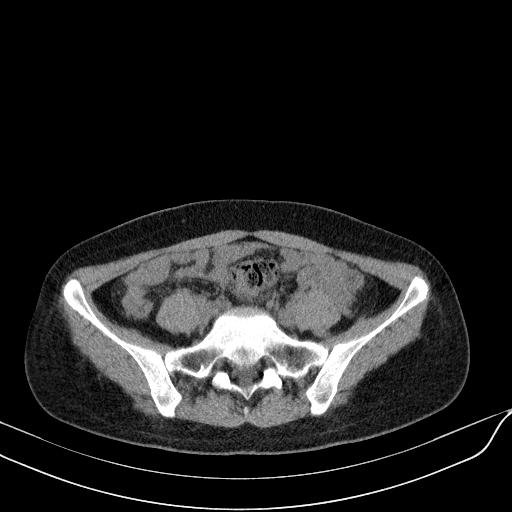

标题: CT23965:无外伤史,下腹痛 [打印本页]

标题: CT23965:无外伤史,下腹痛

肠道未准备,继续往下扫,乙状结肠占位不排除。建议钡灌或结肠镜检查。

乙状结肠占位不排除

扫描时应做肠道准备,口服稀释造影剂。

回肠间质瘤?

肠道肿瘤,建议行钡剂灌肠检查。